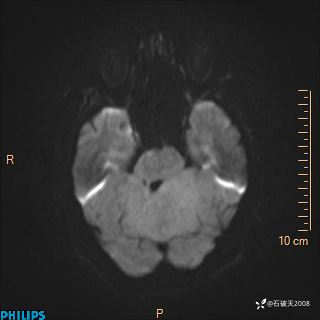

DWI

ADC